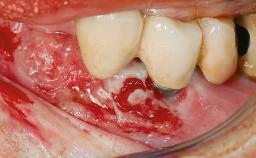

A 66-year-old patient presented because of retention loss of the tooth-supported FDP in the right maxilla (x-13-x-11). The mandibular full-arch implant-supported reconstruction (x-i34-i33-x-x-x-x-i43-i44-x) had suffered extreme wear. His medical history revealed high blood pressure, controlled with anti-hypertensive medication. The patient was a light smoker (2 to 3 cigarettes per day). The existing reconstructions had been performed alio loco about five years previously. That treatment had taken an extensive amount of time, and as early as during the fabrication of the reconstructions, multiple complications had occurred with the provisionals.